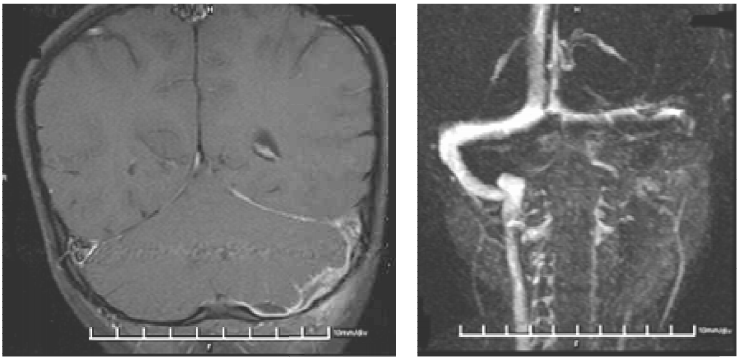

38 一位 28 歲女性已有一個半月月經沒來,近兩日常感覺右下腹疼痛,今日則因疼痛加劇而就醫,經陰 道指診發現子宮有觸壓疼痛的情形,同時子宮右邊處亦有觸壓疼痛的情形。尿液懷孕試驗呈現陽性反應,超音波掃描發現右邊卵巢(ROV)旁有囊狀腫塊,大小約 2.5×2.8 公分(箭頭所指之處), 此患者最適合之診斷為:

(A)輸卵管外孕(tubal pregnancy)(B)卵巢腫瘤(ovarian tumor)(C)輸尿管水腫(hydroureter)(D)輸卵管卵巢膿瘍(tubo-ovarian abscess)